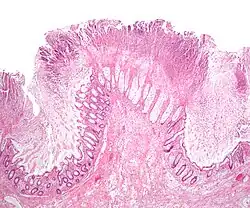

Micrograph of a colonic pseudomembrane in C. difficile colitis, a type of pseudomembranous colitis, H&E stain

Before the advent of tests to detect C. difficile toxins, the diagnosis most often was made by colonoscopy or sigmoidoscopy. The appearance of "pseudomembranes" on the mucosa of the colon or rectum is highly suggestive, but not diagnostic of the condition.[46] The pseudomembranes are composed of an exudate made of inflammatory debris, white blood cells. Although colonoscopy and sigmoidoscopy are still employed, now stool testing for the presence of C. difficile toxins is frequently the first-line diagnostic approach. Usually, only two toxins are tested for—toxin A and toxin B—but the organism produces several others. This test is not 100% accurate, with a considerable false-negative rate even with repeat testing.[47]